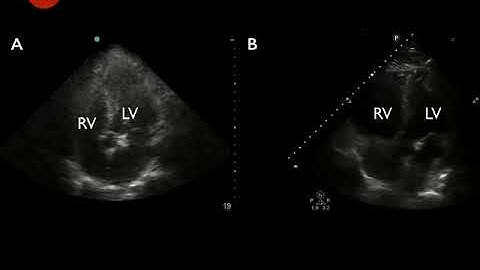

Apical 4 Chamber normal